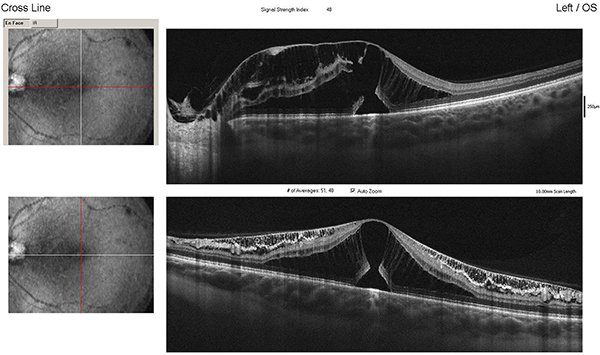

Paciente de sexo masculino de 47 años, sin antecedentes patológicos generales ni oculares de relevancia que consultó por guardia, derivado con diagnóstico de desprendimiento de retina en ojo derecho de un mes de evolución. Al ingreso presentaba una agudeza visual en ojo derecho (OD) de 5/10 sin corrección 10/10 con corrección (+1,50) y en ojo izquierdo (OI) 10/10 sin corrección. Test de Amsler alterado en OD. A la biomicroscopía ambos ojos se presentaban sin particularidades. Presión intraocular: 12/14 mmHg. Fondo de ojo derecho: papila bordes netos, excavada 0,7 atrofia peripapilar, pliegues maculares e impresionaba líquido subretinal; y en OI: papila bordes netos excavación 0,3, mácula de características normales, retina aplicada. Ante el diagnóstico presuntivo de coriorretinopatía central serosa (CCS) de OD solicitamos tomografía de coherencia óptica en donde observamos desprendimiento del neuroepitelio con compromiso de gran parte de la mácula (fig. 1). Pedimos ionograma sérico (no patológico) e iniciamos tratamiento vía oral con eplerenona 25 mg/día y tópico con bromfenac 1 gota cada 6 horas. A las dos semanas el paciente asistió a control sin mejoría de la visión (AV mejor corregida de 7/10) y sin cambios en el fondo de ojo. Realizamos nuevo OCT y vimos un aumento del líquido subretinal y retinosquisis parafoveal hacia nasal (fig. 2). Realizamos 3 inyecciones mensuales intravítreas de anti-VEGF (bevacizumab) y aumentamos la dosis de eplerenona a 50 mg/día durante 30 días, sin respuesta. A los tres meses, la AVMC era de 1/20, en el fondo de ojo, además de los pliegues maculares, observamos múltiples exudados duros maculares. Realizamos ecografía ocular a fin de descartar otras causas de desprendimiento seroso de retina y retinofluoresceinografía (RFG) en búsqueda de punto de fuga, sin hallazgos de interés (fig. 3).

Figura 1. OCT de ojo derecho con desprendimiento seroso del neuroepitelio.

Figura 2. OCT de control de ojo derecho con persistencia del desprendimiento seroso y retinosquisis.

Al no presentar respuesta ante los tratamientos recibidos, reinterpretamos el cuadro clínico, observando detenidamente en el fondo de ojo derecho y en OCT una lesión compatible con foseta del disco óptico con filtración de líquido hacia el espacio subretinal (figs. 4 y 5).